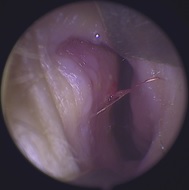

| 疾病類別: | 兒童耳鼻喉科 |

| 疾病名稱: | 鼻過敏和流鼻血 |

這是一個小孩鼻部流鼻血的照片,小朋友過敏性鼻炎常會忍不住抓鼻孔、揉鼻子造成鼻黏膜受傷,圖中左側是鼻中隔,右側是鼻甲骨及腫脹的鼻黏膜,圖中可以看到在鼻中隔的位置有一個出血點,這是鼻子最容易出血的位置,大約就在鼻孔進去不到1公分的距離,不管是揉鼻子或是挖鼻孔都是容易在這位置製造傷口。